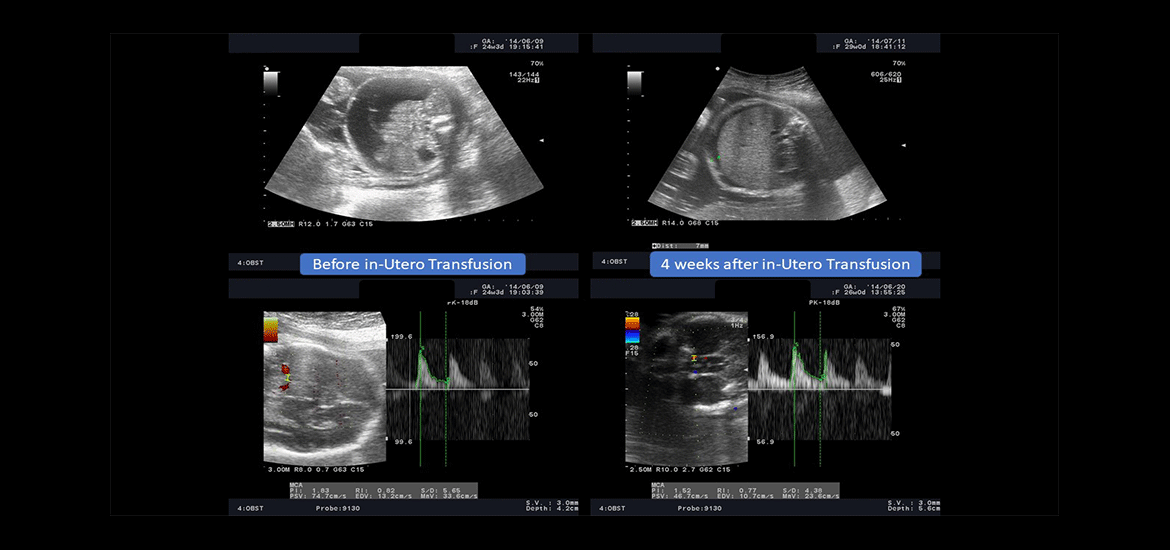

Dr Abi Nader’s main research interests relate to fetal medicine and female urinary incontinence.

Pregnancy